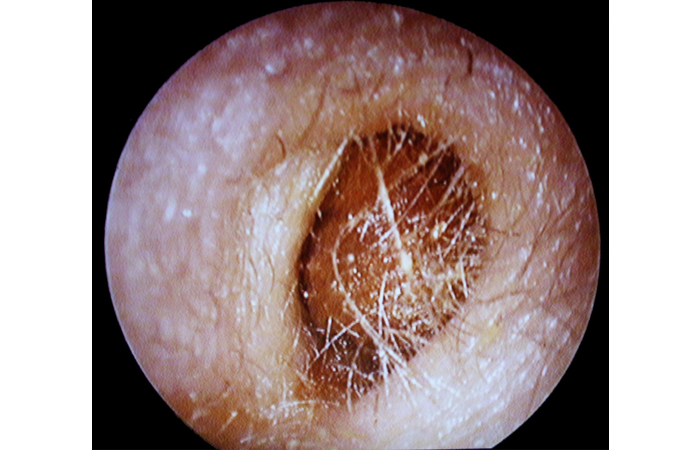

The main impediments to seeing the eardrum clearly are debris or inflammation of the ear canal (usually due to otitis externa), or wax, which appears as a yellowy, orange or brown deposit (see Figure 3).

Otoscopy of excess earwax

Source: Descouens D. Own work, CC BY-SA 3.0 (commons.wikimedia.org/w/index.php?curid= 8371534)